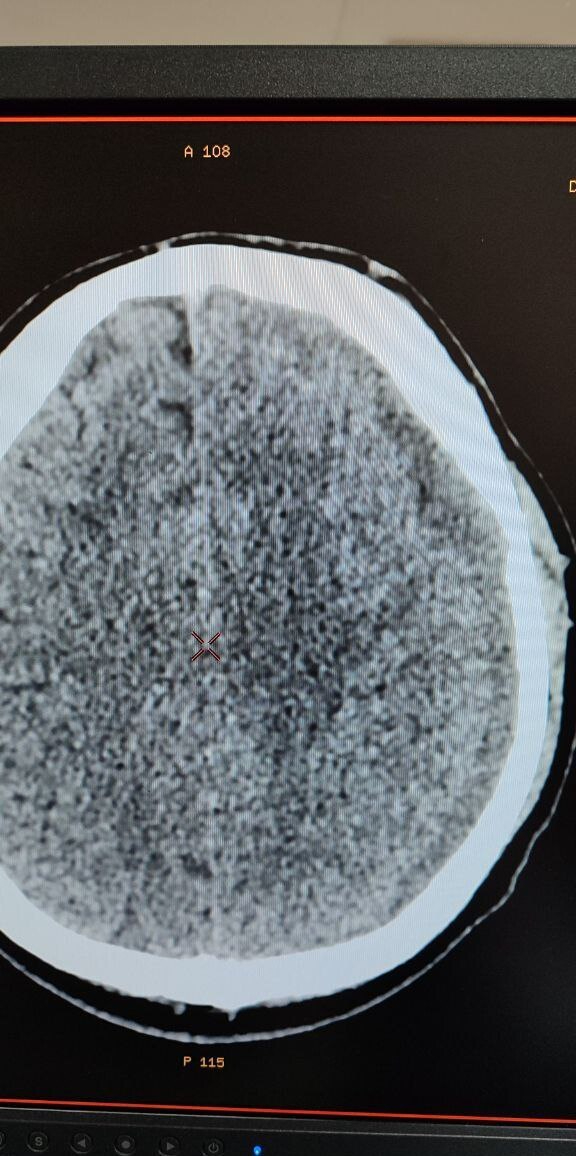

Метод был успешно применен у 39-летнего пациента, поступившего в нейрохирургическое отделение 18 декабря 2025 года, через 12 суток после получения тяжелой черепно-мозговой травмы. На СКТ в тот же день диагностированы очаги контузии обоих полушарий головного мозга и небольшого объема субдуральная гематома слева, вызвавшая значительное смещение структур головного мозга.

После детального обследования хирург Александр Майоров предложил применить новую тактику. Уже через четверо суток контрольная СКТ показала значительный регресс гематомы (не менее 20%) и уменьшение смещения мозга с 4 мм до 2 мм.